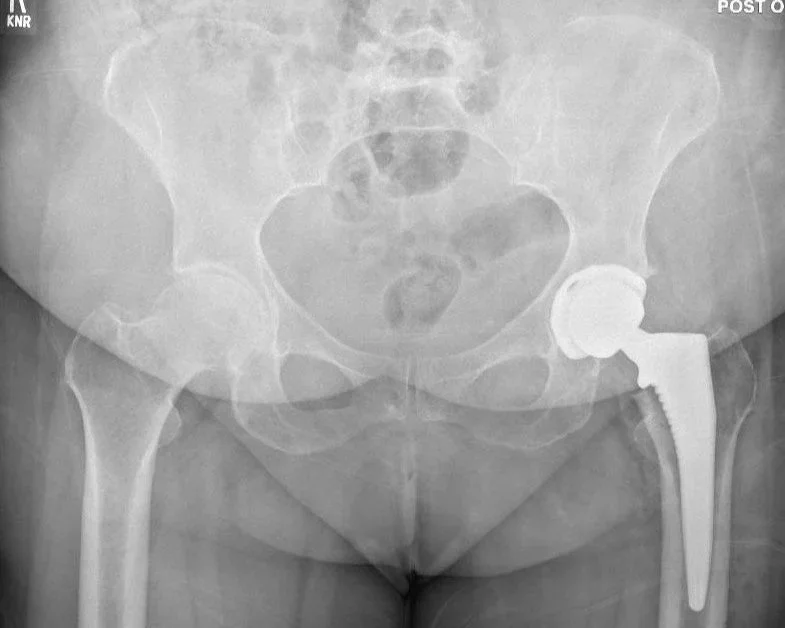

The anterior total hip replacement is a minimally invasive approach for hip replacement surgery where the surgeon accesses the hip joint from the front (anterior) of the hip. Unlike traditional posterior or lateral approaches, the anterior method avoids cutting major muscles, which can result in a quicker recovery.

Useage of X Ray Intraop: Easy to get a perfect AP x ray during surgery which allows for more accurate placement of components in the ideal position